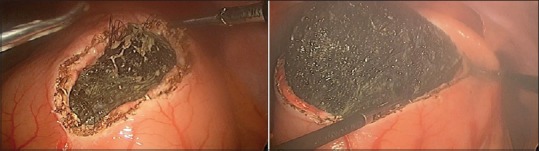

Bezoars are usually defined as collections of nondigestible matter that most commonly accumulates in the stomach and can sometimes extend to the small bowel. Trichobezoars are a rare entity which is most commonly observed in young psychiatric females with trichotillomania and trichophagia. Here, we report a case of giant gastric trichobezoar and a novel technique of laparoscopic removal in a 16 year old female with trichophagia. The giant gastric trichobezoar weighing about half a kilogram was removed en masse laparoscopically by a novel technique. She had an uneventful postoperative recovery and was discharged after psychiatric counseling.